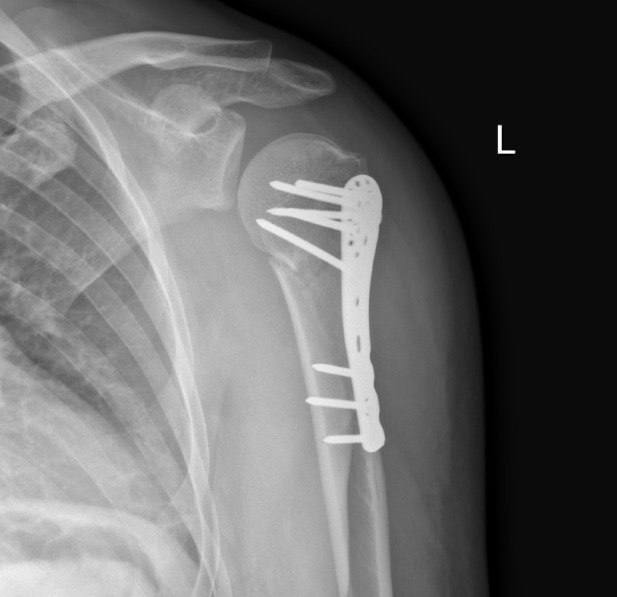

Перелом плечевой кости и остеосинтез

Коротко об одном из видов фиксации костей при переломах:

Остеоси́нтез - хирургическая репозиция костных отломков при помощи различных фиксирующих конструкций, обеспечивающих длительное устранение их подвижности. Цель остеосинтеза — обеспечение стабильной фиксации отломков в правильном положении с сохранением функциональной оси сегмента, стабилизация зоны перелома до полного сращения.

Результат покатушки: Перелом верхнего конца плечевой кости закрытый.

Операция была ночью, укол в шею был достаточно болезненный но минут через 5 после него у меня перестала болеть рука от слова совсем. Убедившись в том что рука онемела, врачи начали резать мою плоть. Прикосновения скальпеля к коже я прекрасно чувствовал но это не было больно. Без длительно ожидания мне начали в катетер добавлять пропофол после чего картинка в глазах поплыла и единственное что я помню - врач анестезиолог сказала "заказывай сон". Очнулся я под конец операции но отчётливо помню звук работы "шуруповёрта" при помощи которого мне крепили пластину к кости но я к этому так спокойно относился, по всей видимости из-за пропофола который мне дали что бы спал. Самым больным и неприятным в операции для меня было - зашивка нитками, почему то анестезия тут не работала и пришлось терпеть, благо процедура заняла по ощущениям не более 5 минут.